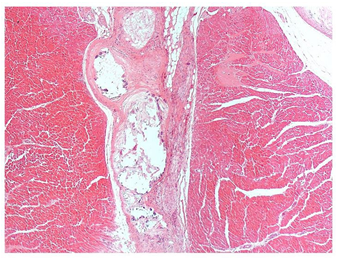

La tiroides mostró una severa atrofia folicular generalizada, folículos reducidos de tamaño e irregulares, la mayoría perdieron el coloide o permanecieron con escaso coloide condensado, áreas de infiltración de tejido adiposo en el intersticio (Figuras 4 y 5), múltiples focos de infiltrado de linfocitos y células plasmáticas, con predominio de los primeros, cambios ateroscleróticos en vasos arteriolares.

Figura 5 Tiroides: Inflamación difusa de tipo linfoplasmocitario y severa atrofia de folículos, los cuales carecen de coloide en el lumen (200X, H&E).